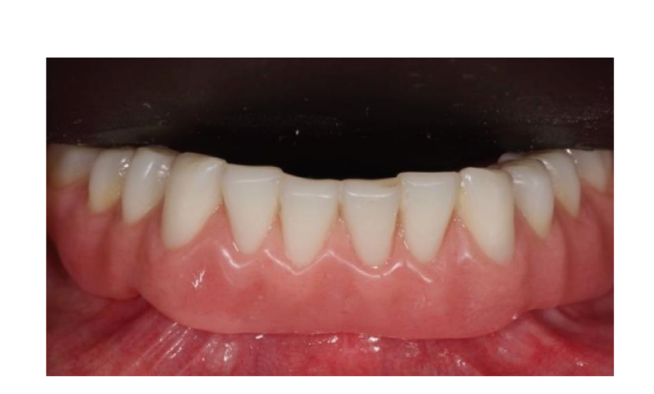

Dopo l'intervento, ai pazienti è stato consigliato di evitare qualsiasi trauma nel sito chirurgico, comprese le procedure di spazzolamento. È stata prescritta una dieta fredda e morbida post-chirurgica. Dopo l'intervento, ai fumatori è stato consigliato di astenersi dal fumo per due settimane. Sono state fornite istruzioni dettagliate per l'igiene orale, inclusa la raccomandazione di sciacquare tre volte al giorno con clorexidina allo 0,12%. Sono stati prescritti analgesici, come 600 mg di ibuprofene o alternative simili, secondo necessità. I punti di sutura sono stati tipicamente rimossi entro un periodo di dieci a quattordici giorni. Secondo un flusso di lavoro precedentemente riportato, le procedure protesiche sono iniziate otto settimane dopo l'inserimento degli impianti. Secondo un protocollo di carico precoce, una nuova dentiera rimovibile completa rinforzata in metallo è stata consegnata in entrambi i gruppi entro quattro settimane dopo l'inserimento degli impianti. Dopo due o tre giorni, gli abutment di guarigione sono stati svitati e gli attacchi sono stati collegati a lato della poltrona alla nuova protesi rimovibile. I pazienti sono stati randomizzati per ricevere attacchi OT Equator® (Rhein’83, Bologna, Italia) nel gruppo di test o attacchi Locator (Zest Anchors LLC) nel gruppo di controllo. I sistemi di attacco randomizzati sono stati posizionati e serrati secondo le istruzioni del produttore. Nel gruppo di test (Figure 1–5), dopo la guarigione gengivale, i più recenti attacchi OT Equator® a basso profilo sono stati avvitati sugli impianti utilizzando il cacciavite quadrato OT Equator®, con un intervallo di coppia di 22–25 Ncm. Le altezze dei manicotti variavano da 0,5 a 7,0 mm, a seconda delle dimensioni della zona di transizione di ciascun impianto, facilmente misurabili utilizzando il misuratore di altezza del manicotto millimetrico a codifica colore (Rhein’83, Bologna, Italia) dopo la rimozione dell'abutment di guarigione. Successivamente, è stato preparato lo spazio necessario per accettare la gabbia in acciaio della sede femminile nella superficie di adattamento della dentiera rimovibile completa mandibolare. Dischi protettivi in silicone (Rhein’83, Bologna, Italia) sono stati posizionati sopra gli attacchi OT Equator®. Cappucci di ritenzione extra-morbidi (giallo, 600 g) sono stati inizialmente inseriti nella sede femminile in acciaio, attaccati a OT Equator®, e infine fissati alla dentiera utilizzando resina acrilica autoindurente. Allo stesso tempo, il paziente ha tenuto le dentiere in occlusione, direttamente a lato della poltrona. Dopo la completa polimerizzazione, la dentiera è stata prelevata e i dischi in silicone sono stati rimossi. L'eccesso di acrilico è stato rifilato e la dentiera è stata rifinita e lucidata. Un mese dopo la consegna delle protesi, i cappucci di ritenzione gialli sono stati sostituiti con un tipo più robusto (rosa, 1200 g).

Nel gruppo di controllo (Figure 6–10), l'attacco Locator (Zest Anchors LLC) è stato avvitato sugli impianti utilizzando il cacciavite Locator (Zest Anchors LLC), con un intervallo di coppia di 20–25 Ncm. Le altezze delle maniche di 2,5 o 4,0 mm, a seconda della dimensione della zona di transizione di ciascun impianto, sono state misurate utilizzando la sonda profonda della linea di impianti dopo la rimozione dell'abutment di guarigione. Successivamente, sono stati preparati spazi per accettare la gabbia in acciaio della custodia femminile sulla superficie di adattamento della protesi totale rimovibile mandibolare. Anelli bianchi protettivi in silicone (Zest Anchors LLC) sono stati posizionati sopra gli attacchi Locator. Cappucci neri passivi sono stati utilizzati per caricare l'attacco, attaccato al Locator, e infine fissato alla protesi utilizzando resina acrilica autoindurente, mentre il paziente teneva le protesi in occlusione, direttamente a fianco della poltrona. Dopo la completa polimerizzazione, la protesi è stata prelevata e gli anelli bianchi sono stati rimossi. L'eccesso di acrilico è stato rifilato e la protesi è stata rifinita e lucidata. I cappucci neri sono stati rimossi e quelli blu (6N) sono stati montati nella custodia in acciaio. Un mese dopo la consegna delle protesi, i cappucci di ritenzione sono stati sostituiti con una matrice rosa (12N).